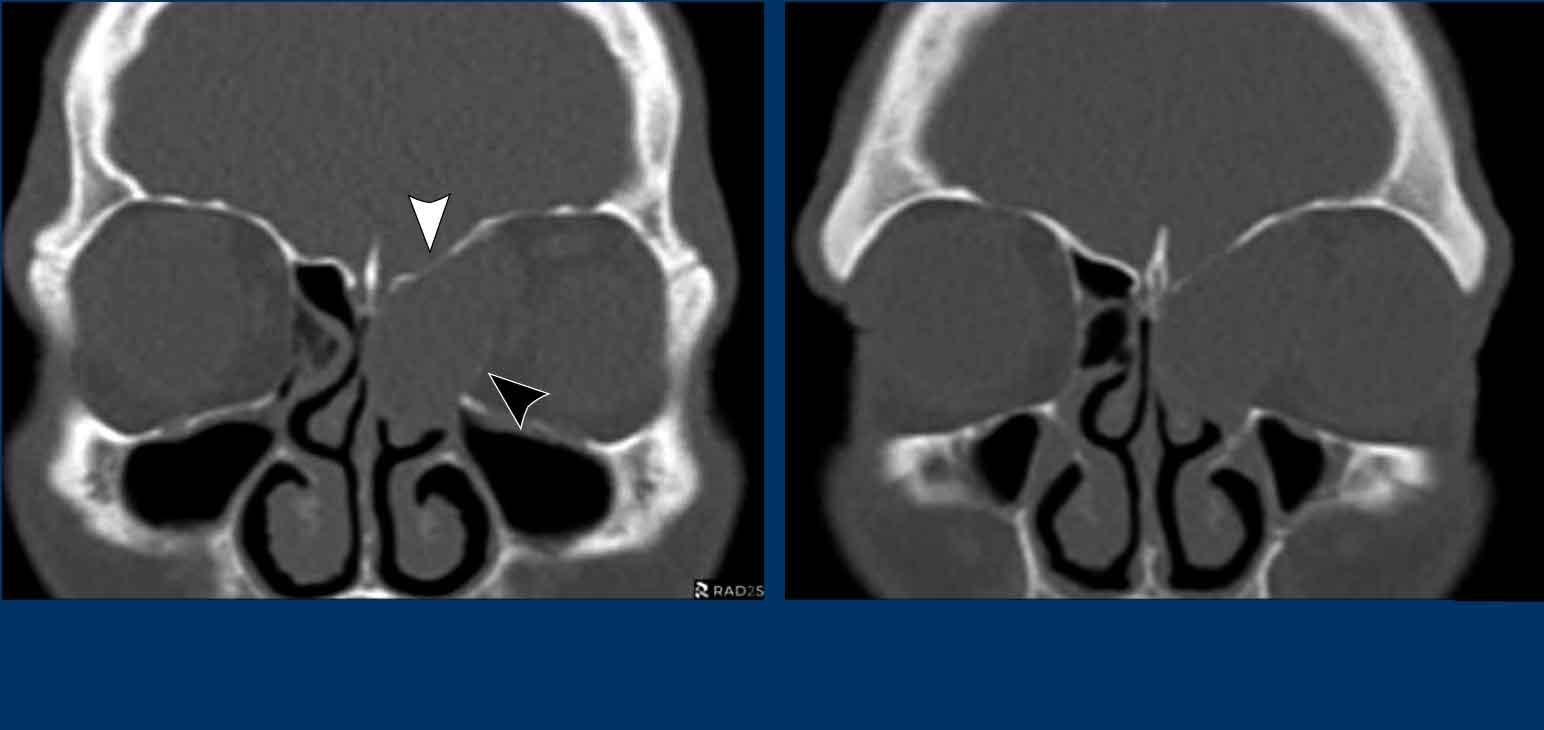

Dưới đây là thêm các ví dụ về nang nhầy.

- Nang nhầy nhỏ

ở xoang bướm.

Xoang bị lấp đầy hoàn toàn bởi mô mềm (tức là chất nhầy) kèm theo giãn rộng với bờ xương xoang còn nguyên vẹn. - Nang nhầy xoang trán.

Đôi khi, bờ xương bị mỏng đi có thể gây nhầm lẫn với phá hủy xương. Trên các lát cắt CT mỏng, thường có thể nhìn thấy cấu trúc xương còn nguyên vẹn. - Nang nhầy của tế bào xoang sàng trước.

- Nang nhầy xoang bướm phải. Vách liên xoang bướm bị đẩy giãn rộng qua đường giữa.

- Nang nhầy xoang trán.

- Nang nhầy xoang sàng phải với tình trạng mỏng và giãn rộng của lamina papyracea vào hốc mắt cùng bên.